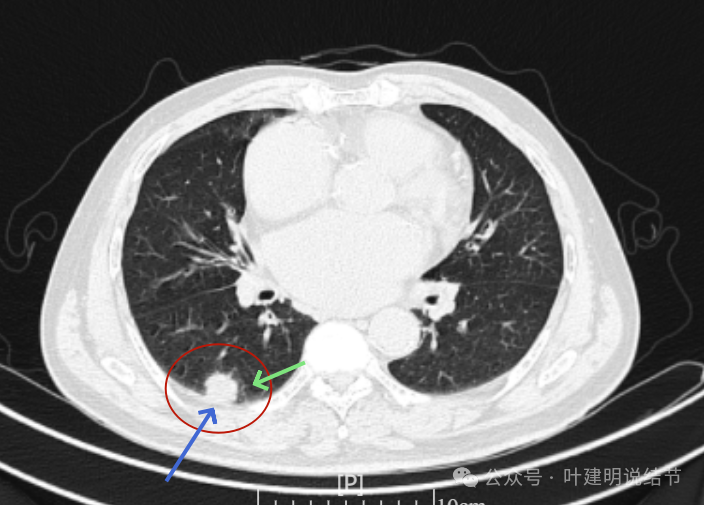

我们先来看2022年3月主要病灶的影像:

右上叶结节实性,密度高,边缘平整,轮廓清楚,像良性些。

右下似见微小结节,实性,与边上小血管截面不太好区分,过小没什么临床意义,能随访。

左下胸膜下实性结节,轮廓稍模糊,密度较高,边缘较光,像淋巴结些,能随访。